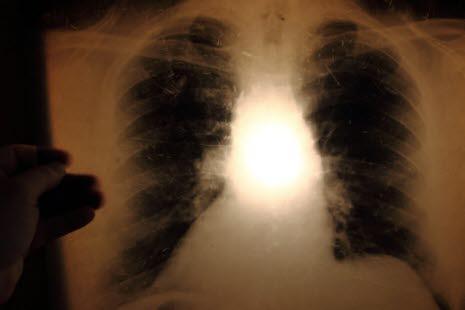

Tuberkulose er en livstruende infeksjon som først og fremst angriper lungene. Symptomer på aktiv tuberkulose er hoste, vekttap og slitenhet. Tuberkulose spres via dråpesmitte.

Tuberkulose er en livstruende infeksjon som først og fremst angriper lungene. Sykdommen dreper hvert år mellom en og to millioner mennesker rundt om i verden (i 2017 var det 1,6 millioner). Verdens helseorganisasjon (WHO) satser mye på å redusere forekomst og antall dødsfall forårsaket av tuberkulose. Minst 100 millioner nye tilfeller med tuberkulose forventes å utvikle seg innen år 2020 og 36 millioner er forventet å dø av sykdommen. I øyeblikket får i gjennomsnitt én person i sekundet tuberkulose - 10 millioner hvert år. Man antar at 30 prosent av verdens befolkning er smittet med tuberkulose (cirka to milliarder). Tuberkulose er uvanlig i Norge. Hvert år diagnostiseres knapt 300 tilfeller av tuberkulose, mest blant innvandrere fra land med høy forekomst av tuberkulose. I 2017 ble det meldt totalt 261 pasienter med tuberkulose i Norge. Av disse var kun 30 (11 %) personer som var født i Norge.